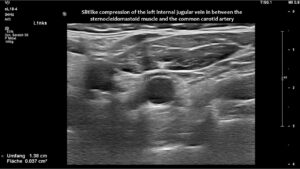

However, in this patient, both jugular veins were compressed. The middle portion of the internal jugular vein was pushed ventrally by the increased cervical lordosis on both sides, becoming squeezed between the carotid artery and the sternocleidomastoid muscle.